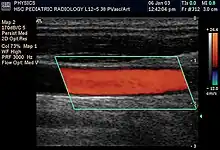

Duplex ultrasonography sometimes refers to Doppler ultrasonography or spectral Doppler ultrasonography.[3] Doppler ultrasonography consists of two components: brightness mode (B-mode) showing anatomy of the organs, and Doppler mode (showing blood flow) superimposed on the B-mode. Meanwhile, spectral Doppler ultrasonography consists of three components: B-mode, Doppler mode, and spectral waveform displayed at the lower half of the image. Therefore, "duplex ultrasonography" is a misnomer for spectral Doppler ultrasonography, and more exact name should be "triplex ultrasonography".[3]

Colour Doppler shows the direction of the blood flow in red or blue (either towards or away from the transducer). Meanwhile, spectral Doppler not only shows the direction of blood flow, it also shows the phases (pulsatility) and acceleration of the blood flow. Any sudden changes in direction of blood flow produces audible sounds on the ultrasound machine.[3]

In spectral Doppler, the y-axis shows the direction and velocity of the flow. Meanwhile, the x-axis (as known as "baseline") shows the flow over time. The gradient at any point on the waveform would therefore shows the acceleration of the flow. In "antegrade" flow, the blood flows according to the normal flow within the circulatory system (e.g. veins flow towards the heart while arteries flows away from the heart). In "retrograde" flow, the flow would reverse (e.g. veins flow away from heart or arteries flow towards the heart). However, "retrograde" flow can be both abnormal or normal. For example, in portal hypertension, there is an abnormal portal venous flow where it flows away from the liver (hepatofugal flow) instead of the normal flow towards liver (hepatopetal flow). In jugular venous pressure waveform of the internal jugular vein, the retrograde "a" waveform is a normal flow due to right atrium contraction. Both antegrade or retrograde flow can be either towards or away from the probe transducer, depending on the position of the probe relative to the blood flow. Blood flow toward the transducer would appear above the baseline while blood flows away from the transducer will appear below the baseline. Waveform of the flow can be classified as: pulsatile (as in arteries), phasic (as in veins), non-phasic (as in diseased veins), and aphasic (no flow). Spectral broadening (thickness of the waveform) increases from large vessels (plug flow) to medium vessels (laminar flow) to small/stenotic/diseased vessels (turbulent flow) due to a larger variety of blood with different ranges of velocities in those with turbulent flow.[3]